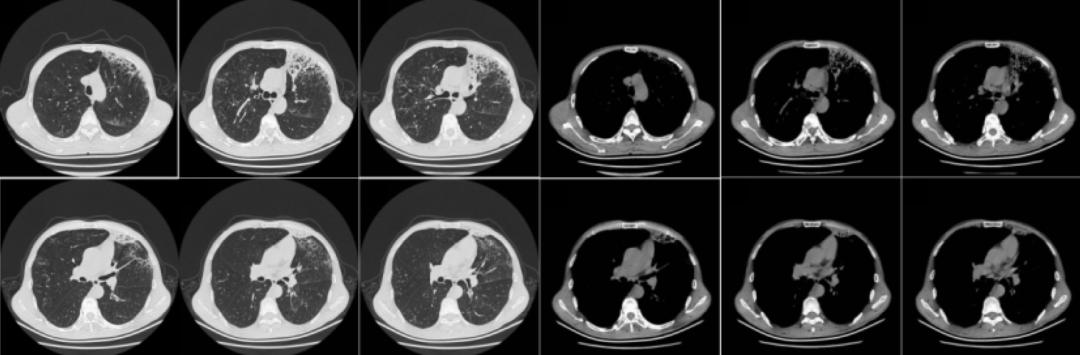

当时为患者查体的情况为:T 36.5 ℃,P 89次/分,R 20次/分,BP 101/76mmHg,全身浅表淋巴结未触及肿大,听诊双肺呼吸音粗,未闻及干湿性啰音。以下为该患2018年1月27日胸部CT的影像学资料:

胸部CT提示两肺可见多发类圆形含气透亮影,两肺可见支气管管径增宽,以左肺上叶为著,呈卷发样,右肺中下叶可见结节样高密度影,较大者位于右肺下叶,直径约1cm,两肺可见多发斑片状高密度影,边界不清,以左肺上叶为著。

入院后,给予患者左氧氟沙星联合依替米星抗感染治疗,2018年2月11日复查胸部CT较2018年1月27日无明显变化。患者自觉抗炎治疗后症状好转,2018年2月11日以「慢性阻塞性肺病,继发肺间质改变」之诊断出院。以下为该患2018年10月11日胸部CT的影像学资料:

胸部CT提示肺气肿、两肺多发肺大泡,两肺间质性炎症伴感染(左肺上叶为主),右肺中下叶结节。此次复查提示左肺上叶病变较前加重,我们建议患者住院再次支气管镜检查,但患者因症状无加重,不愿住院治疗。

2019年3月13日,距离该患上一次住院时隔一年之后,其再次「因胸闷、气短1年余,加重1周」之主诉来我院就诊。以下为其2019年3月12日胸部CT的影像学资料:

胸部CT提示两肺间质性改变并右肺中上叶及左肺炎症,较前增多(2018年10月11日);肺气肿伴肺大泡形成;右肺中叶及两肺下叶结节,较前片变化不著;左侧胸膜增厚。

2018年1月27日:

2018年10月11日:

2019年3月12日:

对比以上这些胸部CT,提示左肺上叶实变影变大,呈蜂窝状,左肺下叶出现磨玻璃影及少许蜂窝影。此时我们考虑患者胸部CT表现的蜂房影、囊腔影是细支气管阻塞的征像,左肺下叶磨玻璃影考虑气性播散,临床高度怀疑肺癌。